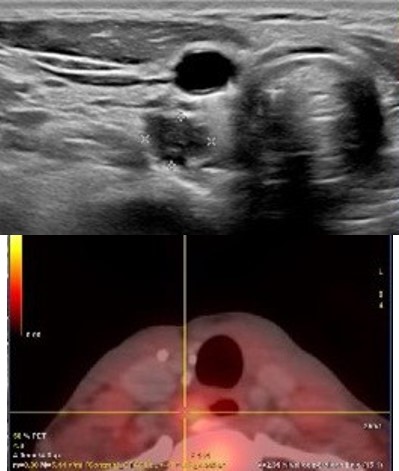

The patient remained disease-free for ten years until new symptoms and biochemical abnormalities reappeared (PTH 229.2 pg/mL, calcium 11.7 mg/dL). Cervical CT and 18F-choline PET-CT identified a hypermetabolic paraesophageal lesion (SUVmax 2.8, 6×7 mm) and three nodules in the upper right thyroid lobe (Figure 1).

Figure 1: (A) Ultrasound: pathological parathyroid gland ultrasound. (B) PET-CT with 18F-Choline: hyperactive parathyroid gland.